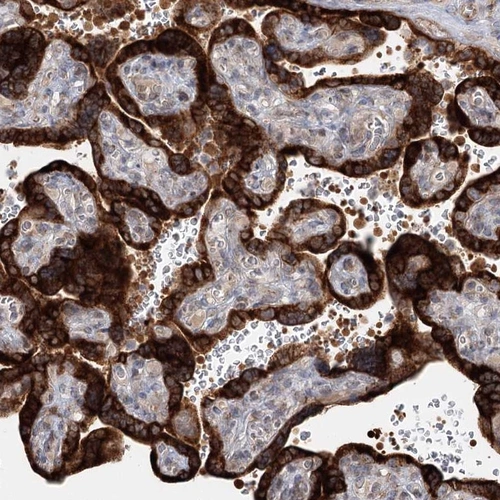

Immunohistochemical staining of human placenta shows strong cytoplasmic positivity in trophoblastic cells.